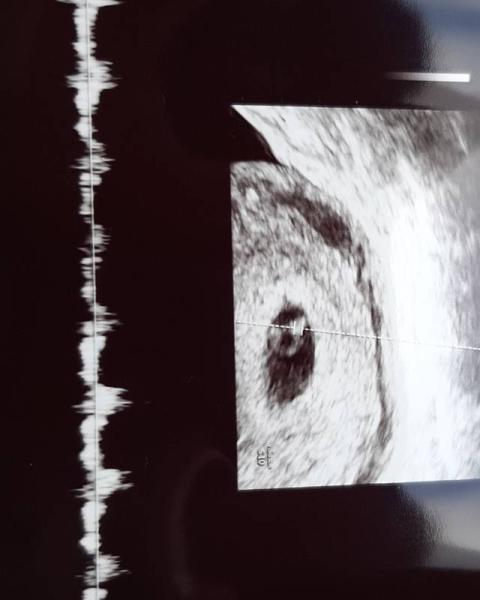

Hallo Mädels Heute hatte ich wieder einen US wegen kurzer Blutung letzter Woche. Mein ET ist der 26.7.2021 und es sieht super aus. Sogar das kleine hat geschlagen. Traumhaft Mein FA meinte ich werde engmaschiger kontrolliert und auch parallel vom pränataldiagnostiker begleitet wegen meiner Vergangenheit. Heute also 6+0 was rechnerisch mit meiner Periode passt. Das kleine Würmchen war 3mm groß

Bild zu Ultraschall 😍 - Forum für Juli - Mamis